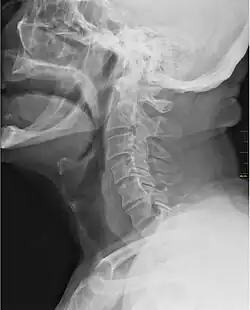

Hrdlo je v lidské anatomii označení pro vnější přední část krku nacházející se před obratlem. V rámci lidského těla se jedná o místo vstupu do hltanu a hrtanu. Významnou součástí hrdla je příklopka hrtanová, která odděluje jícen od průdušnice, což zajišťuje, že konzumovaná potrava nebude vdechnuta do plic.

Součástí hrdla jsou také hlasivky, mandle (krční a nosní) a čípek patrový. Hrdla savců se skládají ze dvou kostí, jazylky a klíční kosti. Hrdlo funguje v koordinaci s dalšími částmi krku a hlavy (ústa, uši, nos) a s některými dalšími částmi těla.

S ústy je v hrdle propojen hltan, což umožňuje vznik řeči v hlasivkách a zároveň postup konzumované potravy hrdlem do žaludku k jejímu zpracování. S nosem je hrdlo propojováno pomocí nosohltanu a s ušima pak Eustachovou trubicí. V hrdle se dále nachází průdušnice, které vedou vzduch do průdušek a následně do plic; díky tomu je zajištěn proces dýchání. V hrdle mají dále nezastupitelnou funkci mandle, které jsou tvořeny lymfatickou tkání a pomáhají zabraňovat různým infekcím. V nejspodnější části hrdla se nachází hrdelní žíla.